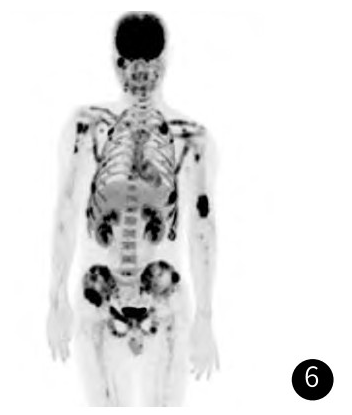

超声提示:甲状腺左侧叶下极旁低回声结节,内部回声不均,CDFI:内可见丰富血流信号,考虑甲状旁腺腺瘤。甲状旁腺显像提示:甲状腺左叶下极结节状放射性浓聚影,提示为功能亢进的甲状旁腺瘤。PET-CT提示:甲状腺左侧叶结节,代谢未见异常;全身多发骨质破坏并软组织肿物形成,代谢增高。

图6 PET-CT示全身多发高代谢肿物。

MRI表现为多囊样肿物,T1等信号,T2压脂序列呈不均匀高信号为主,增强扫描不均匀明显强化,周围软组织水肿,与钱占华等人的总结一致。PET-CT表现为高代谢肿物。甲状旁腺表现为:腺体增大,CT增强明显强化;超声提示丰富血流信号;甲状旁腺显像阳性。